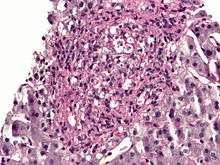

Histoplasma. PAS diastase stain.

Histoplasma in a granuloma. PAS diastase stain.